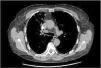

Embolia pulmonar por material de vertebroplastia: otra posible complicación de los asmáticos graves

Pulmonary embolism due to vertebroplasty material: another possible complication of severe asthmatics